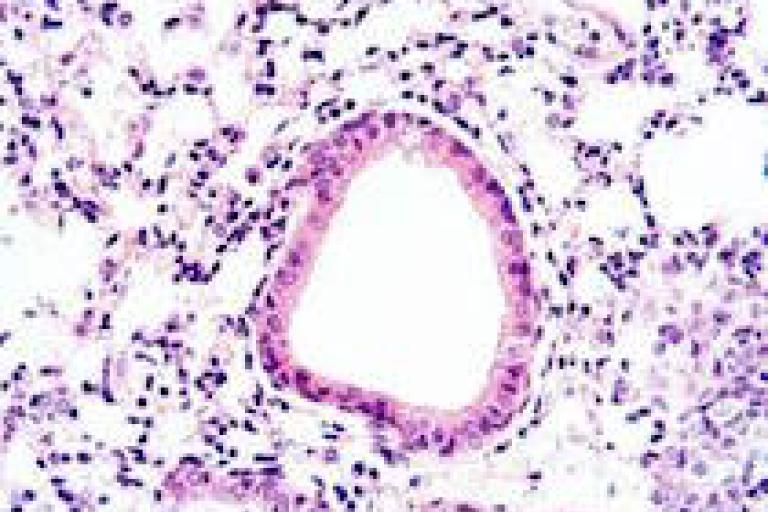

Image: Histology of lungs from our mouse model of Pseudomonas aeruginosa infection.

We use murine models of acute and chronic infection with Pseudomonas aeruginosa in wild-type and CFTR-null mice to determine the impact of sex hormones on inflammation and bacterial clearance.

Male and female mice, both intact and ovariectomized, undergo hormone manipulation to determine specific receptor influences and target pathways. We employ a array of techniques such as immunohistochemistry, flow cytometry, and RT-PCR.